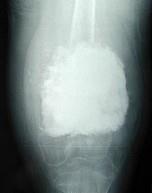

问题 女,10岁,左大腿疼痛,夜间加重,肿胀明显,请结合影像图像,最可能的诊断是()

选项 A.成骨性骨转移 B.化脓性骨髓炎 C.骨肉瘤 D.骨化性肌炎 E.以上都不正确

答案 C